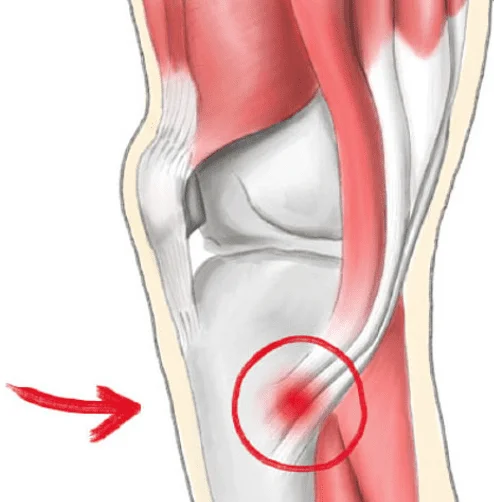

Pes Anserine Bursitis

Cause

Inflammation of the bursa located near the inner knee, often caused by overuse, improper footwear, running, or sudden increases in physical activity.

Symptoms

• Localized pain and tenderness about 2-3 inches below the knee joint.

• Pain worsens with climbing stairs, kneeling, or sitting cross-legged.

• Swelling around the inner knee.

• Pain may worsen at night or after physical exertion.